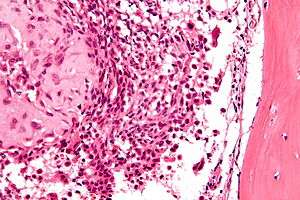

Micrograph of a chondroblastoma. H&E stain. | |

Chondroid differentiation is a common feature of chondroblastoma.[1][4][6] A typical histological appearance consists of a combination of oval mononuclear and multi-nucleated osteoclast-type giant cells.[1][3][4] However this is not a prerequisite for diagnosis, as cells with epithelioid characteristics have been observed in lesions of the skull and facial bones.[4] A "chicken-wire" appearance is characteristic of chondroblastoma cells and is the result of dystrophic calcification that may surround individual cells.[1][5] Although, calcification may not be present and is not a prerequisite for diagnosis.[1][3][4] Mitotic figures can be observed in chondroblastoma tissue but are not considered atypical in nature, and therefore, should not be viewed as a sign of a more serious pathology.[1][4] There is no correlation between mitotic activity and location of the lesion.[4] Furthermore, the presence of atypical cells is rare and is not associated with malignant chondroblastoma.[1][6] There are no discernible histological differences observed when comparing the aggressive form of chondroblastoma that can cause recurrence or metastases with its less aggressive, benign, counterpart.